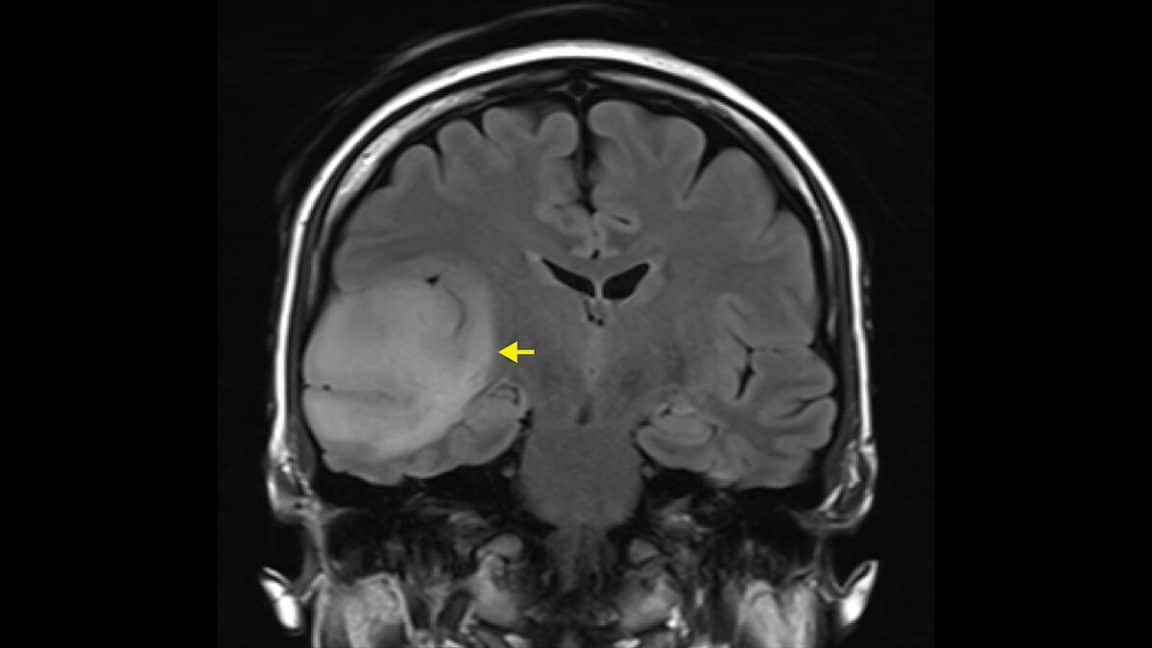

Le glioblastome est le cancer cérébral le plus fréquent chez l’adulte. Il résulte d’une prolifération anormale d’astrocytes, des cellules du système nerveux central. Dans la plupart des cas, le traitement appliqué n’est autre que la chirurgie en association à d’autres thérapies. En France, il y a près de 3 500 nouveaux cas par an avec une durée médiane de survie de seulement seize mois. Et si le glioblastome pouvait bientôt devenir un mauvais souvenir ? Dans un communiqué publié le 12 décembre 2023, la start-up française Hemerion Therapeutics et le CHU de Lille ont détaillé un nouveau traitement, actuellement en cours de test. Or, il utilise la lumière pour cibler et venir à bout de la tumeur.